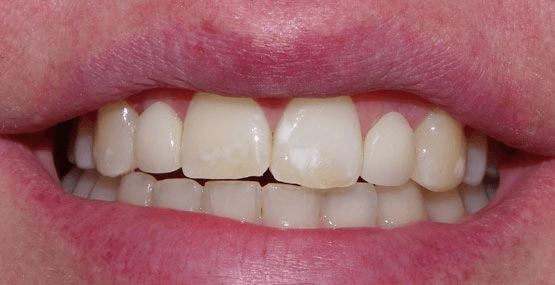

Ultimately, we chose to do two separate bridges out of an all-ceramic material, bonded only to the canines on each side. E.max lithium disilicate bridges from Ivoclar Vivadent 13-X and X-23, cemented by first air abrading the teeth, acid etching with Bisco’s Uni-etch 32% H3PO4 (aq) with BAC, and finally bonding in with Calibra Adhesive Resin cement as per recommended protocol. The results showcase a much more natural smile that’s both brighter and more resilient.